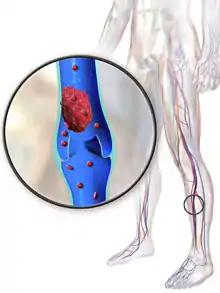

Deep vein thrombosis (DVT) is a type of venous thrombosis involving the formation of a blood clot in a deep vein, most commonly in the legs or pelvis.[9][lower-alpha 1] A minority of DVTs occur in the arms.[11] Symptoms can include pain, swelling, redness, and enlarged veins in the affected area, but some DVTs have no symptoms.[1] The most common life-threatening concern with DVT is the potential for a clot to embolize (detach from the veins), travel as an embolus through the right side of the heart, and become lodged in a pulmonary artery that supplies blood to the lungs. This is called a pulmonary embolism (PE). DVT and PE comprise the cardiovascular disease of venous thromboembolism (VTE).[2] About two-thirds of VTE manifests as DVT only, with one-third manifesting as PE with or without DVT.[12] The most frequent long-term DVT complication is post-thrombotic syndrome, which can cause pain, swelling, a sensation of heaviness, itching, and in severe cases, ulcers.[5] Recurrent VTE occurs in about 30% of those in the ten years following an initial VTE.[3]

Tissue factor, via the tissue factor–factor VIIa complex,[112] activates the extrinsic pathway of coagulation and leads to conversion of prothrombin to thrombin, followed by fibrin deposition.[86] Fresh venous clots are red blood cell and fibrin rich.[42] Platelets and white blood cells are also components. Platelets are not as prominent in venous clots as they are in arterial ones, but they can play a role.[56] In cancer, tissue factor is produced by cancer cells.[84] Cancer also produces unique substances that stimulate factor Xa, cytokines that promote endothelial dysfunction, and plasminogen activator inhibitor-1, which inhibits the breakdown of clots (fibrinolysis).[84]